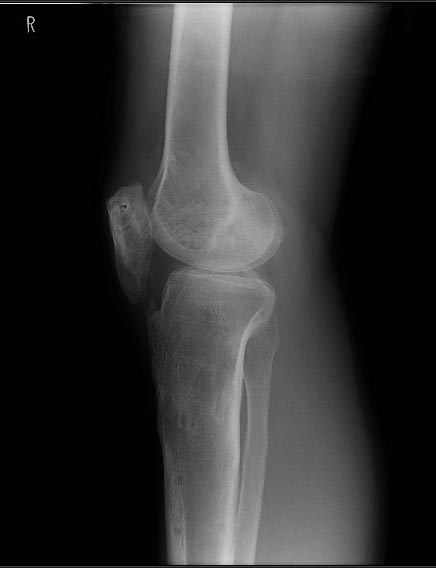

Друзья - коллеги, Пациент 27 лет приехал для удлинения роста по эстетическим показаниям. Метод: крослатеральное двухэтапное удлинение голеней 4см и бедер 3 см. Между этапами удлинения уезжал к себе домой в Японию на реабилитацию. Между этапами удлинения движения в коленных суставах разгибание полное сгибание 90-85. После выписки (февраль 2012) даны соответствующие указание постепенно возрастающей нагрузки и ЛФК коленных суставов.

В настоящий момент жалобы на ограничение сгибания в коленных суставах. Снимки прилагаются.

Возможно( ни в чем не уверен) но причина ,что пошли высоковато ,через бугристось на голенях и собственная связка так же вытягивалась, смещая надколенник вниз? На рентгене же связки оссифицированы,больше справа.

Высылаю снимки, свидетельствующие, что уровень остеотомий вроде как обычный, повторюсь, подобного осложнения после удлинения я не встречал ни у себя ни

в литературе. Сейчас на первое место встает вопрос как помочь данному пациенту. У кого есть опыт лечения patella baja?

Остеотомия высокая, почти на уровне бугристости, так что область прикрепления связки надколенника близко. Я бы делал на 2-3 см ниже. Удлинять на уровне диафиза стало особенно актуально в свете смены аппарата на гвоздь по окончании удлинения.

Лечение - проксимальное перемещение бугристости с частью tibial crest. Как пишут в COO -c"Tibial tubercle osteotomy was originally described for quadriceps relaxation during primary or revision TKA (Fig.7-84). Whiteside and Ohl recommended elevation of an 8- to 10-cm segment of the bone that includes the tibial tubercle and a portion of the anterior crest of the tibia, leaving the anterior compartment musculature attached to the fragment laterally for vascularity. The tubercle can be advanced proximally for patella baja or if the joint line is elevated significantly (Fig. 7-85). They described reattaching the tubercle with multiple wires; other authors have advocated using screws. With secure fixation, passive range of motion can be begun early, but active extension still must be delayed."